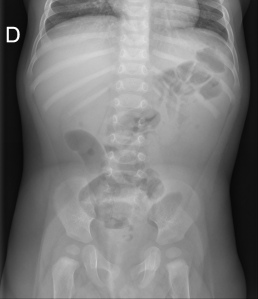

Radiografía simple:

Usada como screening, no excluye un diagnóstico de obstrucción intestinal si es normal.

La OI ha sido una de las indicaciones clásicas para la RA, que es diagnóstica en un 50-60% de los casos, dudosa en un 20-30% y confusa en 10-20% . La sensibilidad oscila entre el 46% y el 90.8% en las diferentes series, con especificidad próxima al 50%.

Los hallazgos principales serían dilatación de asas, niveles hidroaéreos y ausencia de gas distal. Las radiografías de tórax con hemiabdomen superior pueden usarse si existe sospecha de perforación. Tiene importantes limitaciones para determinar la causa de la obstrucion y la presencia de estrangulación.

Placa simple: Triada de Rigler: Obstrucción de asas de delgado + gas en el arbol biliar + litiasis (frec en la FID); estos tres hallazgos constituyen la Triada de Rigler.